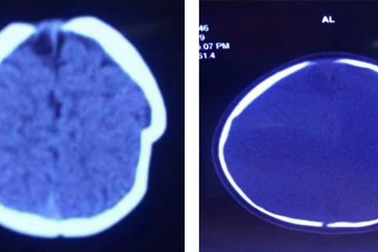

Bé gái 8 tháng tuổi bị lún sọ não vì ngã xe tập điKhi em bé đang ngồi một mình trên xe tập đi, chiếc xe bị tuột mối dây buộc lao xuống sân với độ cao khoảng 1m. Cú va đập mạnh khiến em bé 8 tháng tuổi bị lún sọ não, chóp đầu trái bị lún sâu 1cm.

Chấn thương sọ não vì xe tập điVừa qua, cháu Hùng (Phú Thọ) phải nhập viện trong tình trạng ngủ gà, nôn ói... Qua chẩn đoán bác sĩ xác định cháu bị chấn thương sọ não do va đập.